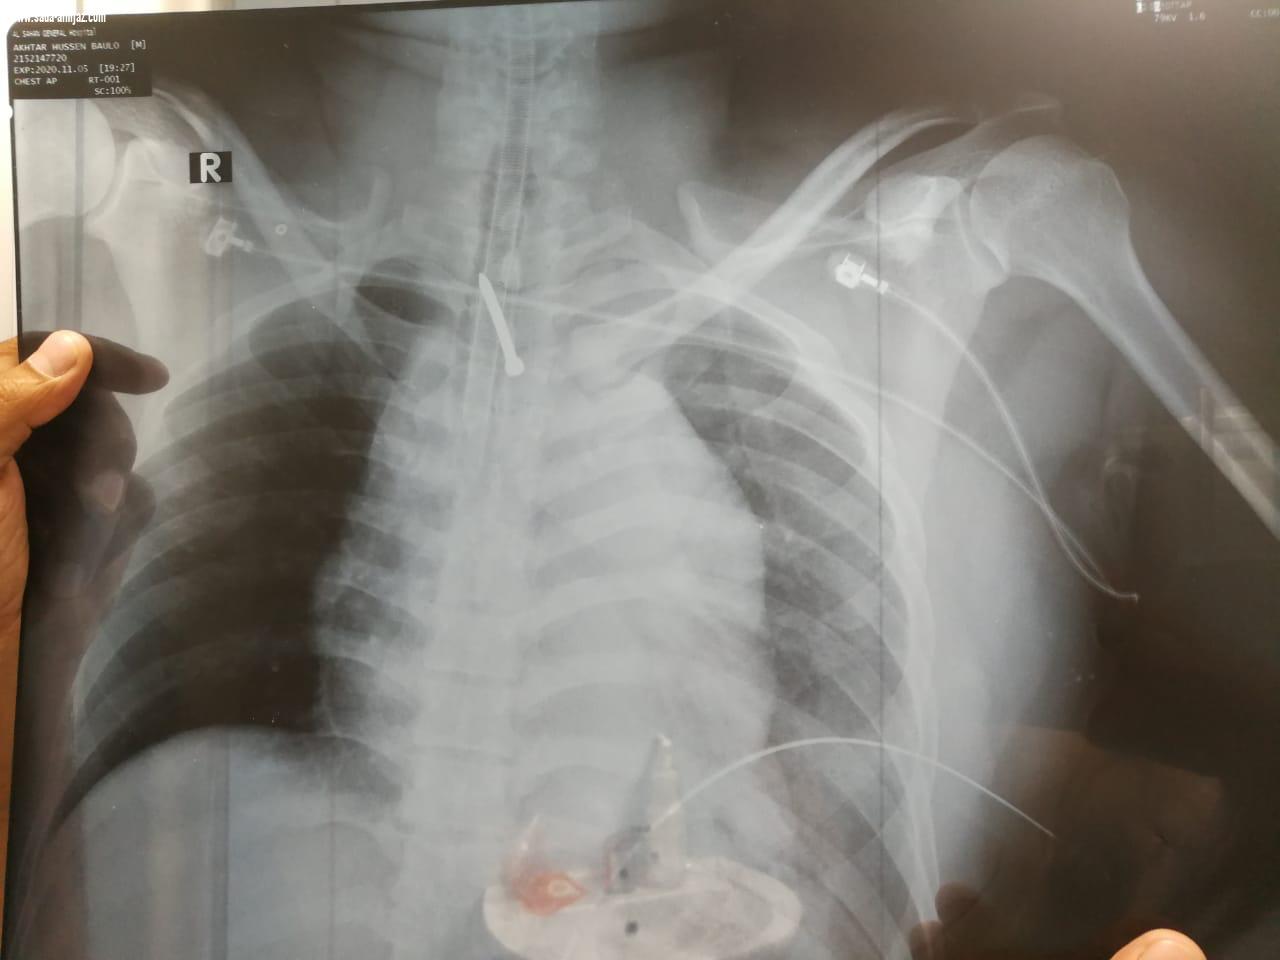

الطائف - عبدالعزيز النفيعي أنقذ الفريق الطبي بقسم جراحة القلب بمستشفى الملك عبدالعزيز التخصصي بمحافظة الطائف حياة عامل بالعقد الرابع من عمره ادخل للطوارئ وهو يعاني من نزيف حاد بالصدر والقلب وتوقف لعضلة القلب . وقد باشر الفريق الطبي الحالة التي تبين أنها تعرضت لارتداد مسمار من مسدس كهربائي كان ييستخدمه العامل نتج عنه إصابه نافذه بالشريان الاورطي الصاعد والغدة التيموسية إضافة إلى إصابة مباشرة للعمود الفقري نتيجة إصابته عن طريق الخطأ بمسمار من حديد "الصلب" عندما كان يستخدم مسدس دقاق كهربائي ارتد عليه بقوة واخترق صدره وأدى إلى حدوث نزيف حاد بالصدر والقلب وتوقف عضلة القلب حيث تم على الفور إجراء عملية انعاش للقلب والرئة وتم نقل المريض إلى غرفة العمليات بصفة طارئة و تم إجراء جراحة لإصلاح الشريان الاورطي المتهتك كما استطاع الفريق الطبي من السيطرة على النزيف بدون الحاجة إلى استخدام جهاز القلب الصناعي وبعد الجراحة تم نقل المصاب إلى قسم العناية المركزة وهو بحالة مستقرة مع توقف كامل للنزيف. وجرى الاستعداد للخطوة التالية والتي تتمثل في استخراج المسمار بعد أن استقرت حالة المريض تم تحديد مكانه عن طريق الأشعة المقطعية و تم استخراج المسمار والذي كان عالقا في أحد فقرات العمود الفقري عن طريق أطباء جراحة المخ و الأعصاب وتشهد حالة المريض الآن تحسنا وقد تم رفع أجهزة التنفس الاصطناعي عنه وهو بحالٍ مستقرة ، ومن المتوقع أن يغادر المستشفى في غضون أيام . والجدير بالذكر أن جراحة القلب هي إحدى التخصصات و الخدمات الطبية الجديدة بمستشفى الملك عبدالعزيز التخصصي والتي تحظى بدعم من إدارة المستشفى ومتابعة مدير الشئون الصحية بالطائف وقاد الفريق الطبي الدكتور حسن صلاح حسن استشاري جراحة القلب والدكتور مروان القصاص استشاري جراحة القلب والدكتور حسين عبدالحميد استشاري و رئيس قسم التخدير والدكتور عبدالله الحارثي استشاري و رئيس قسم العناية المركزة والدكتور عدنان استشاري جراحة المخ و الاعصاب .